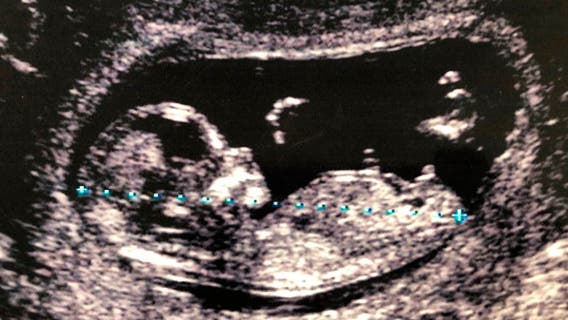

Researchers find microplastics in human placentas for 1st time, calling it 'matter of great concern'

For the first time, researchers have found microplastics in human placentas of four healthy women who had normal pregnancies and births.